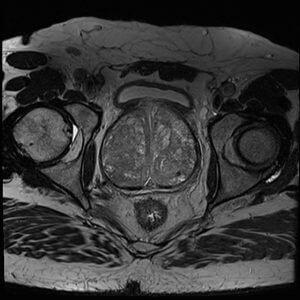

If your doctor mentioned a possible prostate biopsy, you still have options. A prostate MRI (mpMRI) is often used first to help decide whether a biopsy is needed and, if so, where to target it. Below are key facts and smart questions to ask your urologist.

Location and size of suspicious lesions

Likelihood of clinically significant cancer (PI-RADS score 1-5)

Grade and stage indicators

Enables targeted biopsy of suspicious areas (instead of systematic sampling)

Can be fused with real-time ultrasound to guide biopsy in a procedure called MRI/ultrasound fusion biopsy